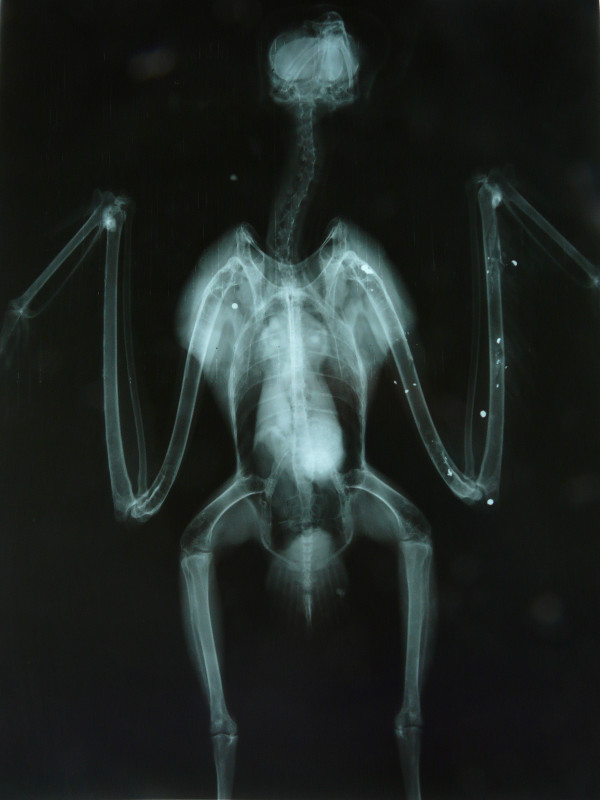

El primero, un ejemplar adulto de milano real ingresó muy aturdido pero con buena condición corporal, lo que nos hizo sospechar que la lesión era reciente. Un gran hematoma invadía toda el ala izquierda y encontramos algunos orificios pequeños en la piel. Se hizo una radiografía para ver el tipo de fractura (hallamos 2 fracturas en vez de una) y si era necesaria o viable la intervención quirúrgica, encontrándonos varios perdigones y numerosos fragmentos de metralla distribuidos por toda el ala y resto del cuerpo. Se aplicaron primeros auxilios y vendaje para inmovilizar la fractura que, afortunadamente, estaba alineada. Gracias a la fluidoterapia y cuidados intensivos el animal se estabilizó y a día de hoy se alimenta con normalidad y su comportamiento es el adecuado. Permanecerá con el vendaje puesto hasta la próxima semana, cuando haremos una radiografía de control para ver si hay formación de callo óseo, podemos retirar el vendaje y valorar el resultado tras este mes en la Enfermería. Se transferirá al departamento de Rehabilitación para empezar con fisioterapia y ver cuáles son las posibilidades reales de liberación de este ejemplar.